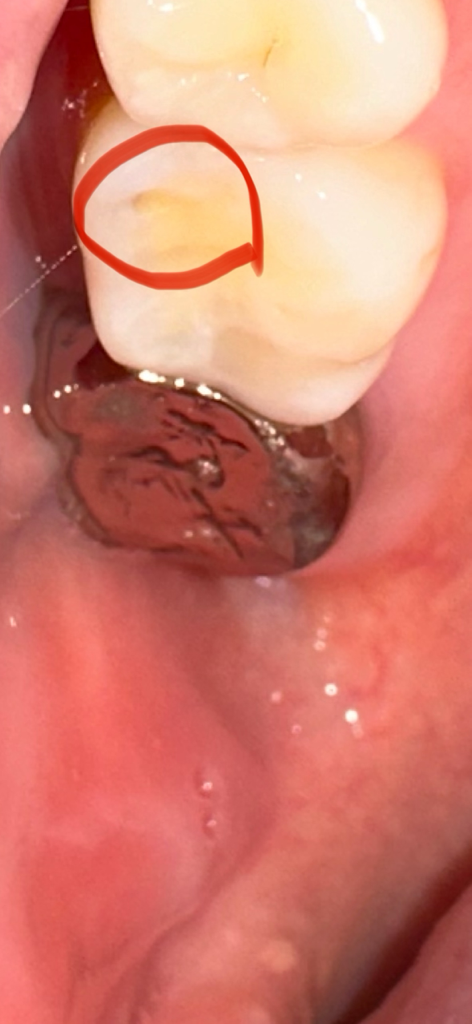

치료를 빨리 해야하고 급한걸까요?

저런 구멍이 없었는데 갈수록 더 커지는거 같아요 ㅠㅠ 치료를 꼭 해야하고 치료가 급할까요?? 통증이나 시린거는 전혀 없습니다 ㅜㅜ 혹시나 나중에 더 심각한 문제가 될까봐 여쭤봐요 ㅠㅠ 구멍 크기도 깊고 많이 큰편인가요?

• 1번 째 사진

구멍이 잇다고 무조건 치료를 하는건 아닙니다. 저부위가 충치때문에 생긴거라면 치료를 하셔야되지만, 교모때문에 생긴거라면 치료를 하지 않으셔도 됩니다.

현재 치아에 충치로 인해 구멍이 생긴것으로 보이며, 방치시에 충치가 더 진행이 되기에 가능한 빠른시일내에 치과에 방문하여 치료를 받길 권합니다.

현재로선 그리 크게 마모되거나 깨진양상은 아니지만 저대로 두면 음식물이 해당부위로 더 잘끼고 향후 치아가 더 깨져나갈 가능성은 있긴 합니다 다만 크기가 아직은 작고 충치도 있어보이지 않으므로 평소 관리를 잘해주면서 딱딱하거나 질긴 음식 줄이기, 이갈이나 이악물기 습관 개선하는 것이 치료를 하는것보다 더 나을 수도 있습니다

사진으로만 봤을 경우에는 마모증으로 보입니다.

마모증은 치아에 강한 힘이 가해지면서 깨지는 증상인데 더이상 크기가 커지지 않기 위해서는 치아에 가해지는 힘을 줄이는거이 좋습니다.

불편감이 있다면 치과용재료로 간단하게 충전을 할 수 있습니다.